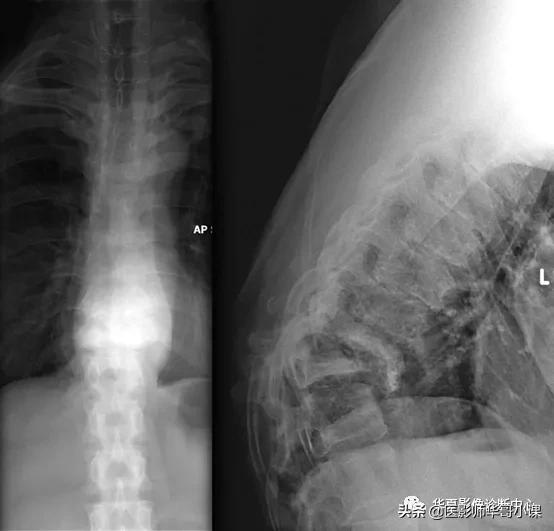

- 脊柱(6%~21%)

- 病因:外伤性脊髓损伤、梅毒的不适当治疗、淀粉样变、对疼痛先天性不敏感、糖尿病

- 部位:胸腰段的连接处、腰椎

- 椎间隙变窄

- 椎骨、椎间小关节溶骨性病变/硬化

- 半脱位

- 突然屈曲

- 脊柱侧凸

- 棘突旁软组织钙化

- 终板较大鸟嘴状骨赘形成

- 多发性骨质碎片、并超出椎体边缘进入椎旁周围肌肉和椎管内

- 鉴别诊断:脊椎骨髓炎、转移瘤、肉芽肿炎

局灶性胸椎后凸是由于严重的结构改变,累及相邻椎体并伴有前屈。